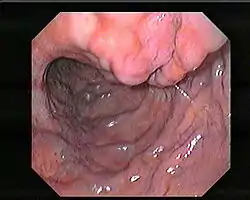

الدوالي المعدية أو دوالي المعدة (بالإنجليزية: Gastric varices) هي عبارة عن أوردة متوسعة متموضعة في الطبقة تحت المخاطية للمعدة، والتي قد تكون مهددة للحياة بسبب النزف الذي تسببه.

يتطلب تشخيص دوالي المعدة غالباً تنظيراً هضمياً علوياً. تشمل الأنواع الأخرى للتصوير المستخدمة لتشخيص دوالي المعدة التصوير المقطعي المحوسب (مع التباين)، الموجات فوق الصوتية عبر البطن مع دوبلر، تصوير الأوعية، تصوير الأوعية بالرنين المغناطيسي، و تصوير وريد الباب.[7]

وهو مبني على نتائج تنظيرية هامة سريرياً. وبالتالي، تم تصنيف نتائج التنظير الهضمي للدوالي المعدية وفقاً لشكلها وموقعها ولونها.[10]

تم تعريف الاحمرار البؤري اللماع ذي الجدار الرقيق على الدوالي كبقعة حمراء اللون (بقعة RC). حيث أن البقعة RC والأشكال الكبيرة للدوالي مرتبطة بخطر أعلى للنزف.